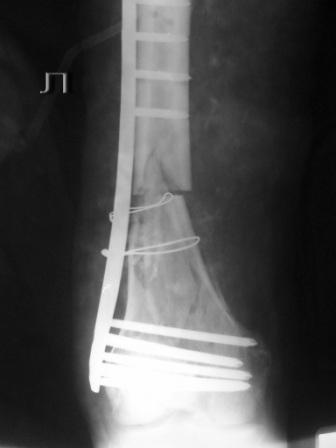

Пациенту 50 лет. 24.11.09 сделали л\бедро.

Оставлен клинически значимый варус, видно градусов 8-10. Для уточнения можно сделать снимок симметричного сегмента и скиаграммы наложить.

Не стоило открывать промежуточные отломки и вязать их проволокой. Это ухудшает их кровоснабжение и может привести к несращению. Не во все случаях, конечно. Удачи.

Сложность репозиции привела к "освобождению" промежуточных отломков - появился значительный костный дефект - пришлось создавать картинку + добавили коллапан.

Не удивляйтесь, если пластина сломается(((

"Мостовидность" вовсе не подразумевает только LCP, также как и LCP не озачает обязательную "мостовидность".

Мостовидность это только часть , так называемого, биологического принципа.Биологический принцип предполагает баланс между механическими свойствами остеосинтеза и сохранением кровоснабжения кости и окружающих мякких тканей. Мостовидная фиксация обеспечивает относительную, эластичную стабильность, которая при малоинвазивной технике (MIPO), т.е, при закрытой репозиции и нескелетировании кости дает хороший шанс на быстрое течение репаративных процессов и сращение перелома.

В Вашем примере, как мне кажется, была довольно травматичная открытая реползиция со скелетированием концов перелома. В результате отсутствует необходимая биологическая составляющая для нормальной репарации кости. кроме того, положение отломков по оси - так себе, и имеется значимый медиалный дефект. Так что к био-логической мостовидной технике фиксации переломов этот случай не имеет никакого отношения. Увы(